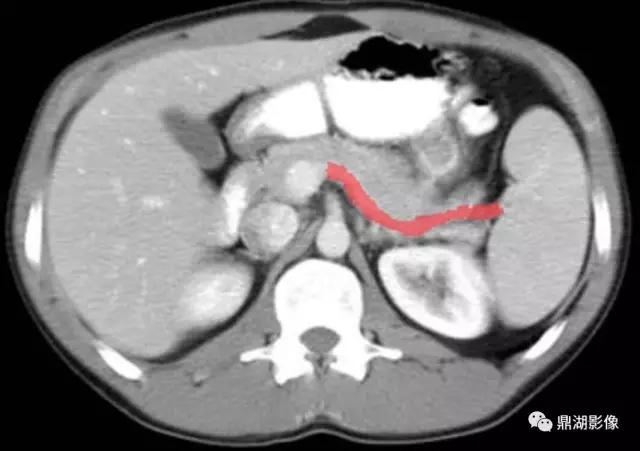

脾静脉(Splenic Vein)

肠系膜上静脉(Superior Mesenteric Vein)

膈肌脚(Curs of Diaphragm)

下腔(Inferior Vena Cava)

十二指肠(Second Portion of the Duodenum)

肠系膜上动脉(Superior Mesenteric Artery)

肝曲(Hepatic Flexure)